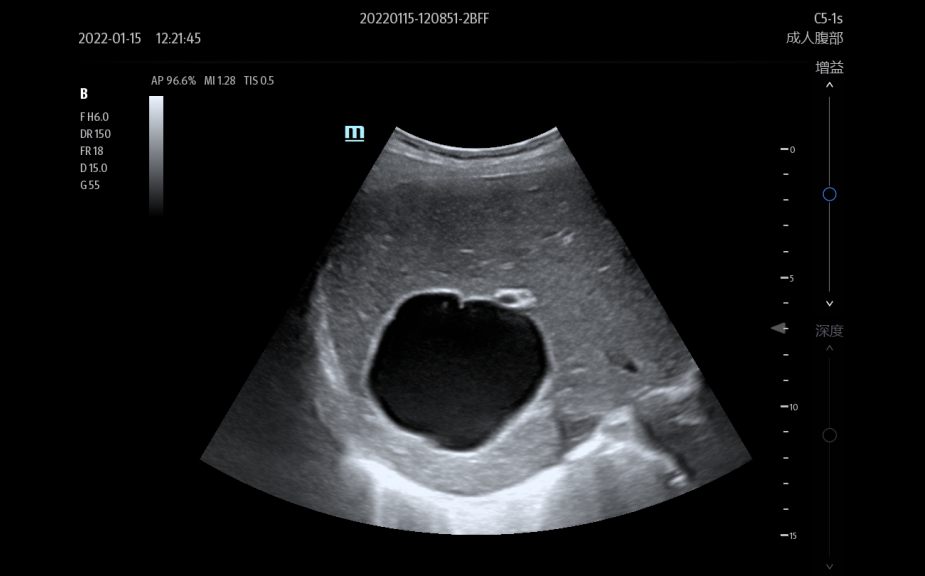

Images

Transducers